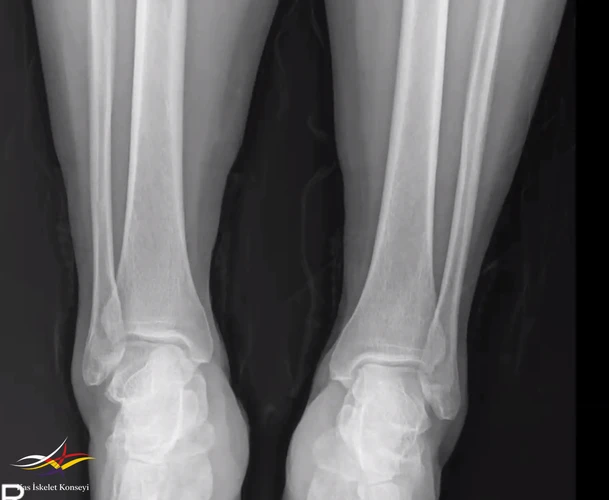

Resim 2. Bilateral ayak bileği grafisi.